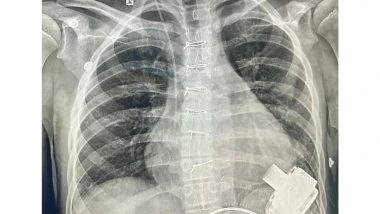

After a complex and difficult surgery that involved connecting a Mechanical Heart Pump to the main pumping chamber of the heart and then connecting the other end (outflow) to the Aorta - the artery that takes blood to various organs of the body. The whole pump is so small that it sits inside the chest and connects to a computerised controller and battery through a small wire that comes out of the skin. As the device was started, it pumped blood from the left ventricle to the body and within a few days in the Pediatric Cardiac ICU, his organ functions started recovering.

After surgery, he has made an extraordinary recovery, from being limited to bed most of the times, he is now walking, going up and down the stairs, has been discharged from the hospital and soon is expecedt to return to his country, go to school, play but with a controller and a battery to remind him of how strong he and his family has been through this dangerous illness.